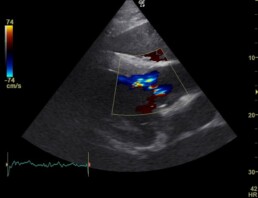

Es wurde eine mittelgradige Aortenklappeninsuffizienz festgestellt. (Abb. 1+2)

Abb.2: RKDLA mittelgradige Aortenklappeninsuffizienz